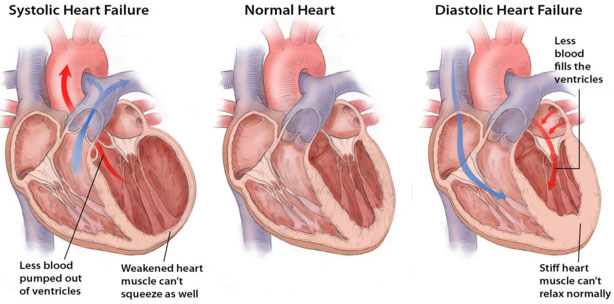

То, что коллаген является основным структурным белком стареющего сердца, обуславливает снижение эластичности органа. При этом мышечные клетки сердца замещаются уже не так быстро, как погибают. Такое слабоэластичное сердце уже не так хорошо наполняется, не так хорошо опорожняется и, соответственно, не так хорошо перекачивает кровь.

Сердечная недостаточность развивается в случаях, когда наносная функция сердца снижается до уровня, не способного обеспечивать кровоснабжение, необходимое для поддержания жизнедеятельности организма. К счастью, это происходит только после того, как колоссальная резервная производительность здорового сердца полностью исчерпана.

Ранее известный как диастолическая сердечная недостаточность диагноз сердечная недостаточность с сохраненной фракцией выброса относится к состоянию, при котором сердечная мышца становится настолько неэластичной, что камеры сердца утрачивают способность полностью наполняться кровью. Даже несмотря на сохранение способности сердца перекачивать кровь, его неспособность наполняться кровью со временем может приводить к задержке жидкости к организме. Это влияет на жизнедеятельность других органов и вызывает застой жидкости, в особенности в легких. Развивающееся в результате плохо поддающееся лечению состояние проявляется очень сильной слабостью и затрудненностью дыхания.

На сегодняшний день эта форма заболевания диагностируется более чем у половины пациентов с сердечной недостаточностью. К ее развитию наиболее склонны женщины и пациенты с сахарным диабетом, ожирением и гипертонической болезнью.

В более раннем исследовании Марбан продемонстрировал способность стволовых клеток регенерировать новую здоровую мышечную ткань сердца после инфаркта миокарда. В своей новой работе он решил изучить возможности использования этих клеток в терапии других заболеваний сердца.

В рамках исследования 34 лабораторным крысам с моделированной гипертонией и сердечной недостаточностью с сохраненной фракцией выброса ввели препарат сердечных стволовых клеток. Группе контроля из 34 животных ввели плацебо. Четыре недели спустя у мышей экспериментальной группы была зарегистрирована нормализация сердечной функции и нормальное наполнение камер сердца. Для животных группы контроля было характерно прогрессирующее ухудшение состояния и преждевременная смерть.

На основании этих результатов Марбан получил разрешение Управления по контролю за продуктами питания и лекарственными средствами США (FDA) на использование кардиосфер (сердечных стволовых клеток) как экспериментального лекарственного средства для лечения пациентов с сердечной недостаточностью с сохраненной фракцией выброса. Препарат таких клеток